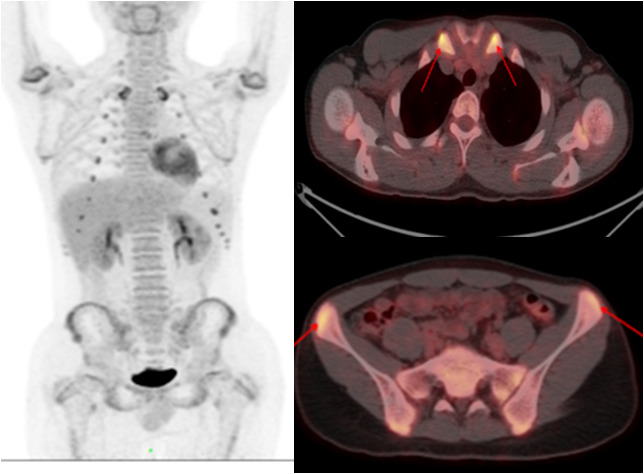

老年男性,反復(fù)發(fā)熱1年余;10年前因主動(dòng)脈夾層行支架植入。PET/CT顯示支架周圍主動(dòng)脈管壁增厚,代謝明顯增高,診斷為支架周圍感染。

少年男性,間斷發(fā)熱半年,一直未找到原因。PET/CT 顯示多處關(guān)節(jié)、軟骨高代謝灶,最終診斷為復(fù)發(fā)性多軟骨炎導(dǎo)致的不明原因發(fā)熱,經(jīng)指導(dǎo)后臨床治療效果良好。